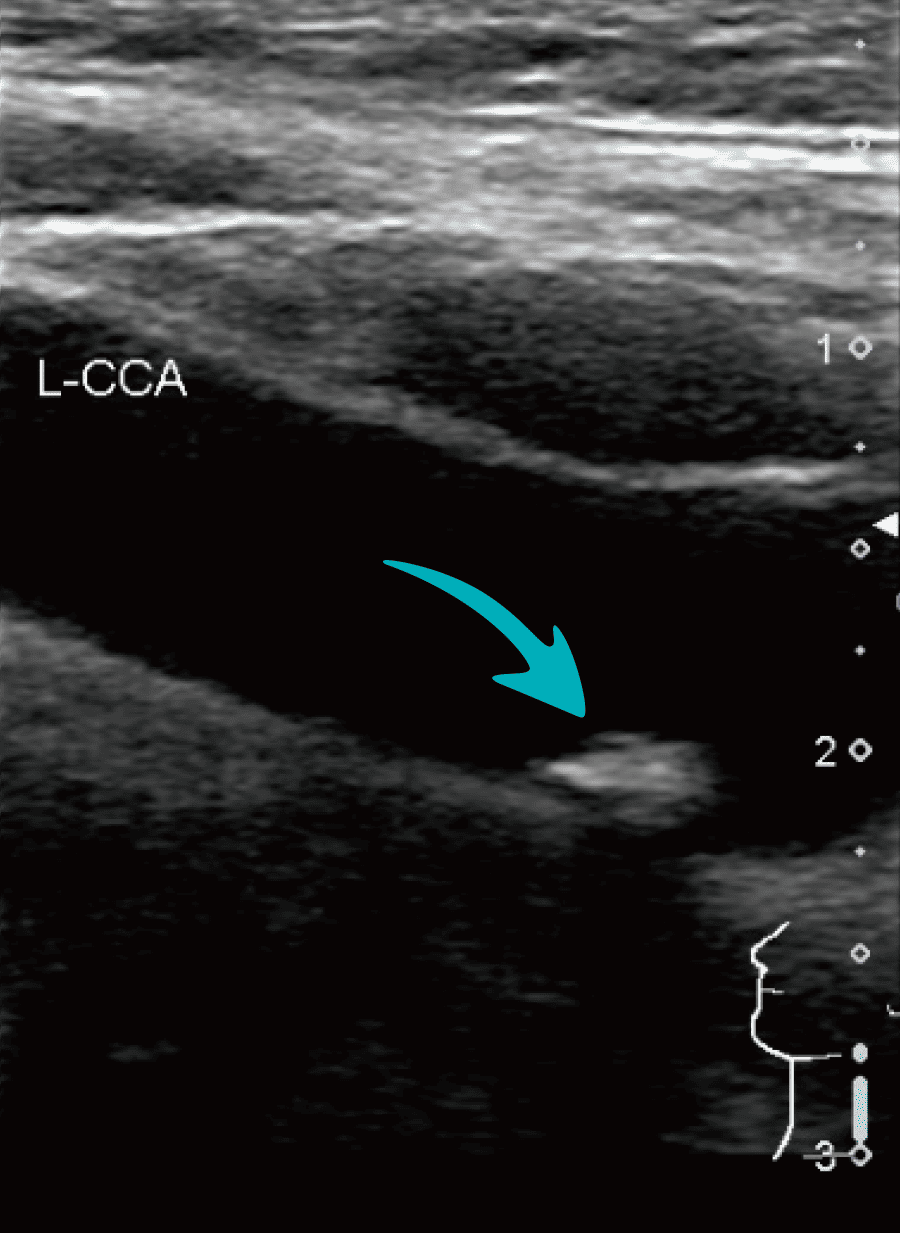

プラーク

低エコープラーク/等エコープラーク/高エコープラーク/不均一エコープラーク

プラークとは血管内にコレステロールや細胞などの粥腫が蓄積した、1.1mm以上の限局性の隆起のことです。厚いプラークがあれば動脈硬化の進行が疑われ、脳梗塞や心筋梗塞などの高リスク群となります。プラークはエコー輝度によって低エコー、等エコー、高エコーに分けられます。低エコーは粥腫や血腫、等エコーは線維組織、高エコーは石灰化病変を示唆しています。なかでも低エコープラークはもろいため、脳梗塞のリスクが高いと考えられています。また、プラークの輝度が均一か不均一かで分類もしています。エコー輝度が複数混在しているプラークを不均一プラークといい、均一プラークに比べて、脳卒中のリスクが高いといわれています。